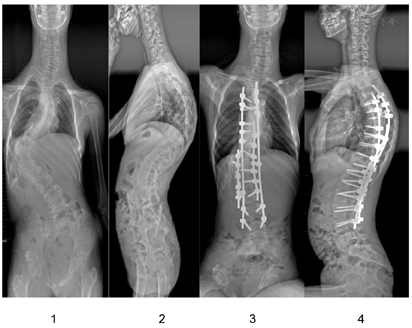

立位全脊柱X线片示脊柱侧弯,胸腰弯cobb角为96°(图4)。全脊柱CT+三维重建示脊柱侧凸、后凸畸形严重,部分腰椎发育不良。心电图、心脏彩超均未见异常。双手手正斜位片示右手第3、4中指节较对侧膨大。双足正位片示右跟骨低密度影右足第3近节趾骨远端、左足第2近节趾骨远端骨性突起。右足第3趾骨远端软组织肿胀(图1)。双下肢血管造影示左侧股动脉下端多发迂曲血管影(图2),左侧髌骨上方肿块邻近髌骨骨皮质破坏,右下肢浅静脉曲张,大隐静脉多发分支与深部血管交通。血常规:中性粒细胞百分率33.8%,淋巴细胞百分率52.7%,单核细胞百分率11.8%,中性粒细胞计数1.6×109/L。生化:碱性磷酸酶249.1 U/L,肌酐34 umol/L,甘油三酯0.40 mmol/L,H-胆固醇2.66 mmol/L,载脂蛋白B 0.49 g/L,其余未见异常。凝血功能:凝血因子Ⅱ 67.5%、Ⅷ 77.2%、Ⅸ 67.0%、Ⅹ 71.8%、Ⅺ 67.1%活性均有所降低,蛋白s活性53.1%也有所下降,余未见异常。

患者6岁时出现跛行步态,X线显示右下肢缩短2 cm,7岁时发现胸腰背部不对称畸形,曾多方就诊,全基因型筛查初步考虑"变形综合征",至当地医院支具保守治疗。近4年来胸腰背部不对称进行性加重,遂至医院就诊。立位全脊柱正侧位片示脊柱侧弯,收住入院治疗。为改善患者畸形体态,防止脊柱侧弯的进行性加重,以及防止脊柱侧弯并发症的发生,于辅助检查完善后行后入路胸腰椎融合术以及T7~L2的8节段的Smith-Peterson截骨术(Smith-Peterson osteotomy,SPO)进行脊柱矫形。手术顺利,术后给予抗感染、止痛、消肿补液对症支持治疗,患者恢复良好,无相关并发症发生,术后X线提示脊柱矫形良好,内固定在位,未见明显松脱及折断征象(图4)。术后6个月以及1年的随访全脊柱X线示患者内固定在位,矫形良好,未出现螺钉松动、近端交界性后凸等并发症(图5)。

对于变形综合征患者的治疗,现在都是对症治疗为主,目前名为Miransertib特异性AKT1抑制剂,脑回状结缔组织痣的大小可以反映其疗效,但其治疗疗效尚未确切,且成本高昂,国内未见该治疗方法[11]。由于PS和脊柱侧凸是2种与身体限制和自尊丧失有关的疾病,并且对这些患者的生存质量有负面影响,因此建议早期诊断和及时治疗。这些患者的脊柱侧凸手术被认为是非常复杂的,有时需要各种截骨术来实现足够的畸形矫正。本例患者的脊柱畸形情况就非常复杂,胸腰段cobb角约96°,且存在严重的后凸畸形。为纠正其畸形,我们实行了后入路胸腰椎融合术以及T7~L2的8节段的SPO进行脊柱矫形,术后患者恢复良好,脊柱形状有了很好的矫正(图6)。我们的经验和结果以及一些其他学者的研究表明,骨科积极的手术治疗可以实现令人满意的畸形矫正,从而提高PS患者的生活质量[12]。